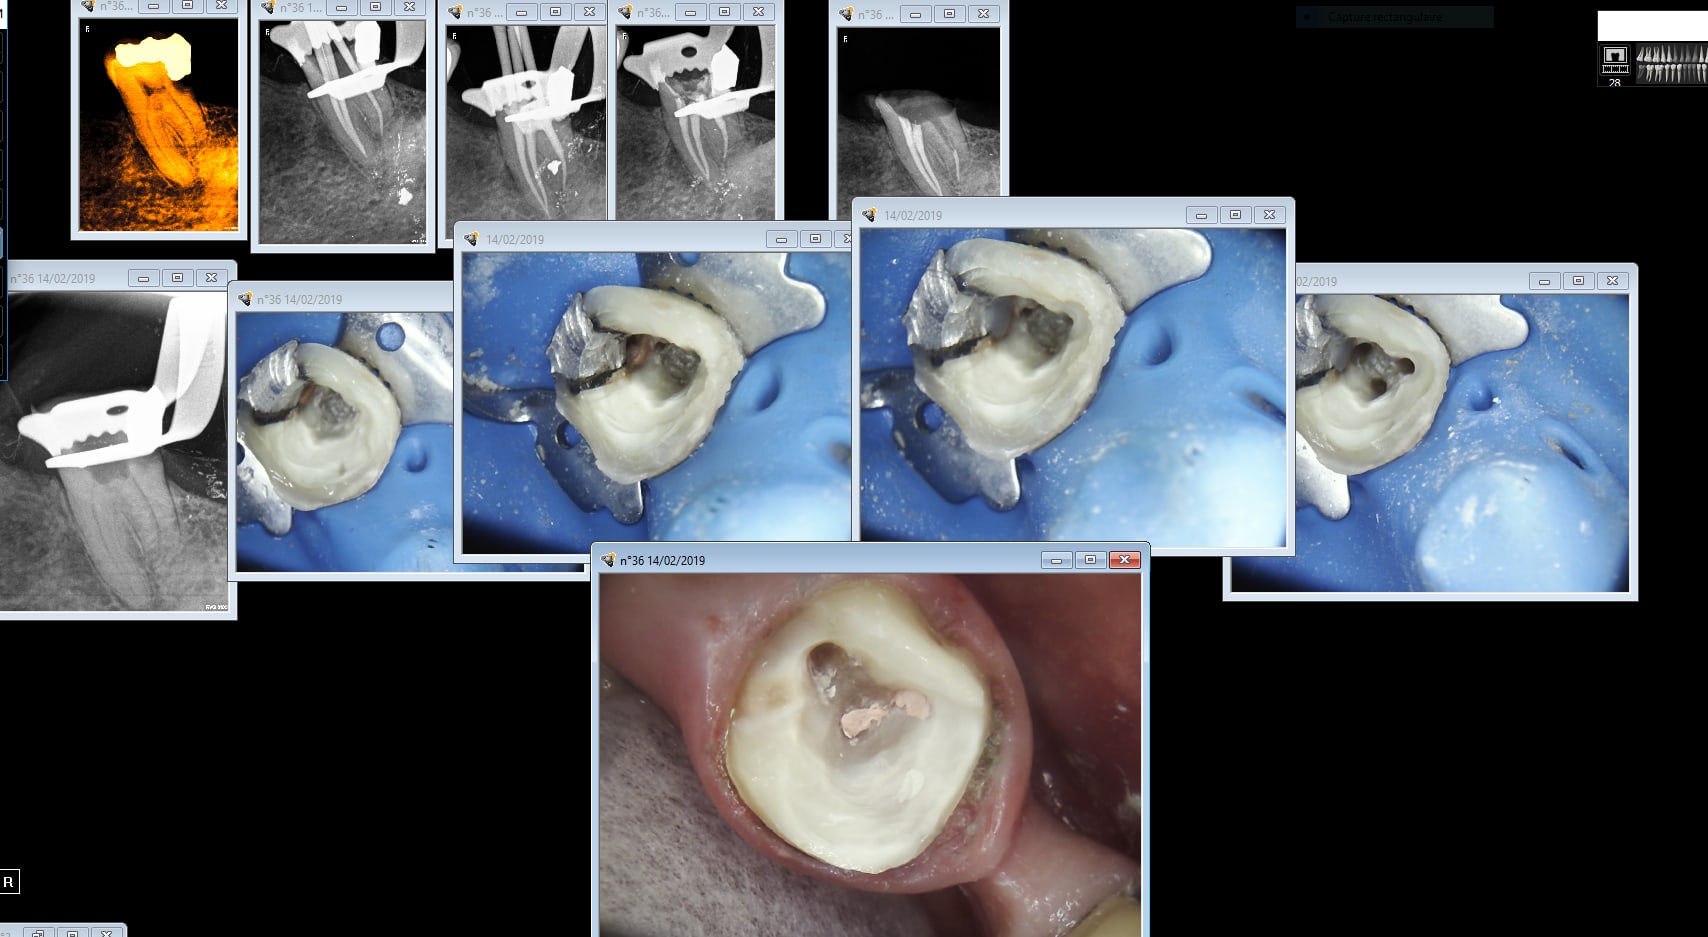

L'imagerie de julie est merdique. L'imagerie CS en revanche c'est de la balle. Je te conseille fortement de l'utiliser avec une passerelle entre julie et CS. Enregistrement par session d'actes ou tu combines photos et radios. Ici " endo taille empreinte 36". Les images apparaitront dans ce classement si je clique sur cette session enregistrée.

Careme 36 chijey - Eugenol

Tu peux importer les radios de julie dans CS si nécessaire. De toutes façons pour que le dossier radio soit à jour tu peux faire les radios recommandées tous les 2 ans. Si tu as des endos pas à l'apex je suppose que les étapes cone en place ont été zappées. -)))